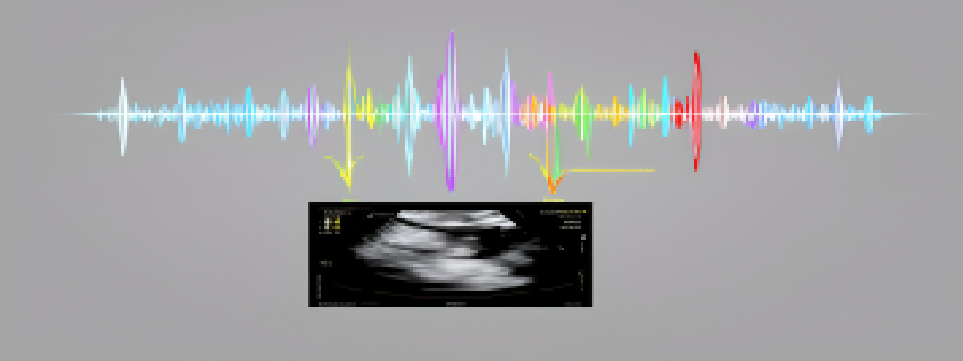

超声检查是利用超声波的“回声游戏”生成图像的无创检查技术。就像蝙蝠靠声波定位,超声探头发射高频声波,遇到不同组织(如肌肉、血管、结石)时,因声阻抗差异产生不同强度的反射回波,计算机将这些回波转化为实时图像。

临床超声主要分为脉冲回声式和多普勒技术两大类,各有侧重用途:

血流评估型:彩色多普勒:用颜色“标注”血流方向——红色朝向探头,蓝色远离探头,亮度代表流速。能直观发现血管狭窄、堵塞等问题,比如颈动脉斑块导致的血流变细。频谱多普勒:以曲线形式精准测量血流速度,常用于诊断先天性心脏病、动静脉瘘等。